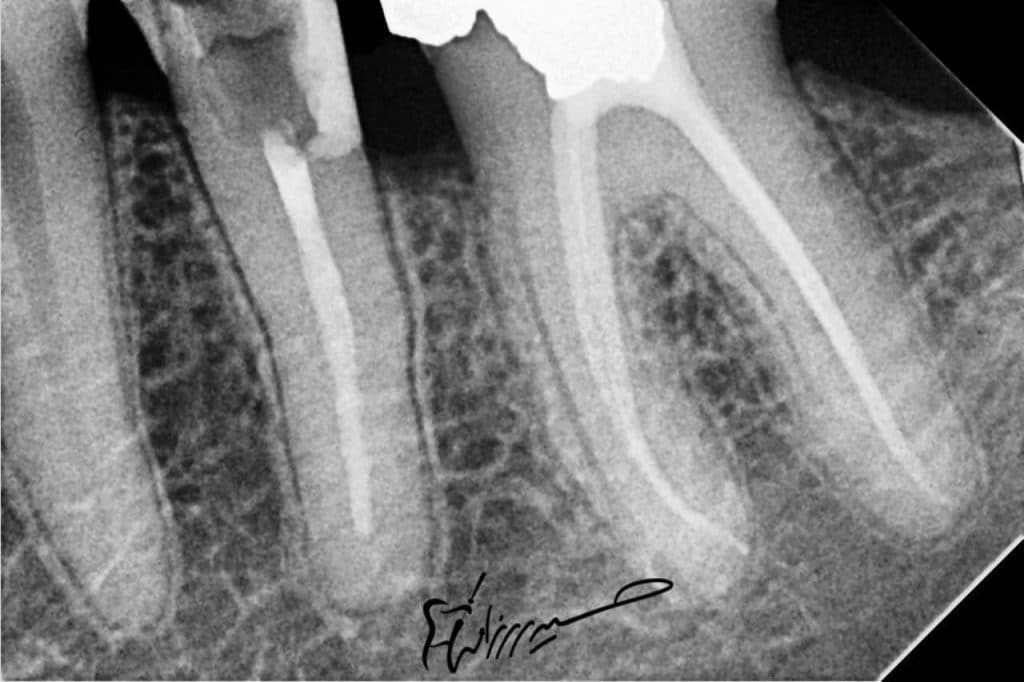

📌 DME confirmed with peri apical radiograph to ensure optimal seal .

📌 Re RCT for tooth no.35 .

DME confirmed with peri apical radiograph to ensure optimal seal .

Now ready for endodontic re treatment